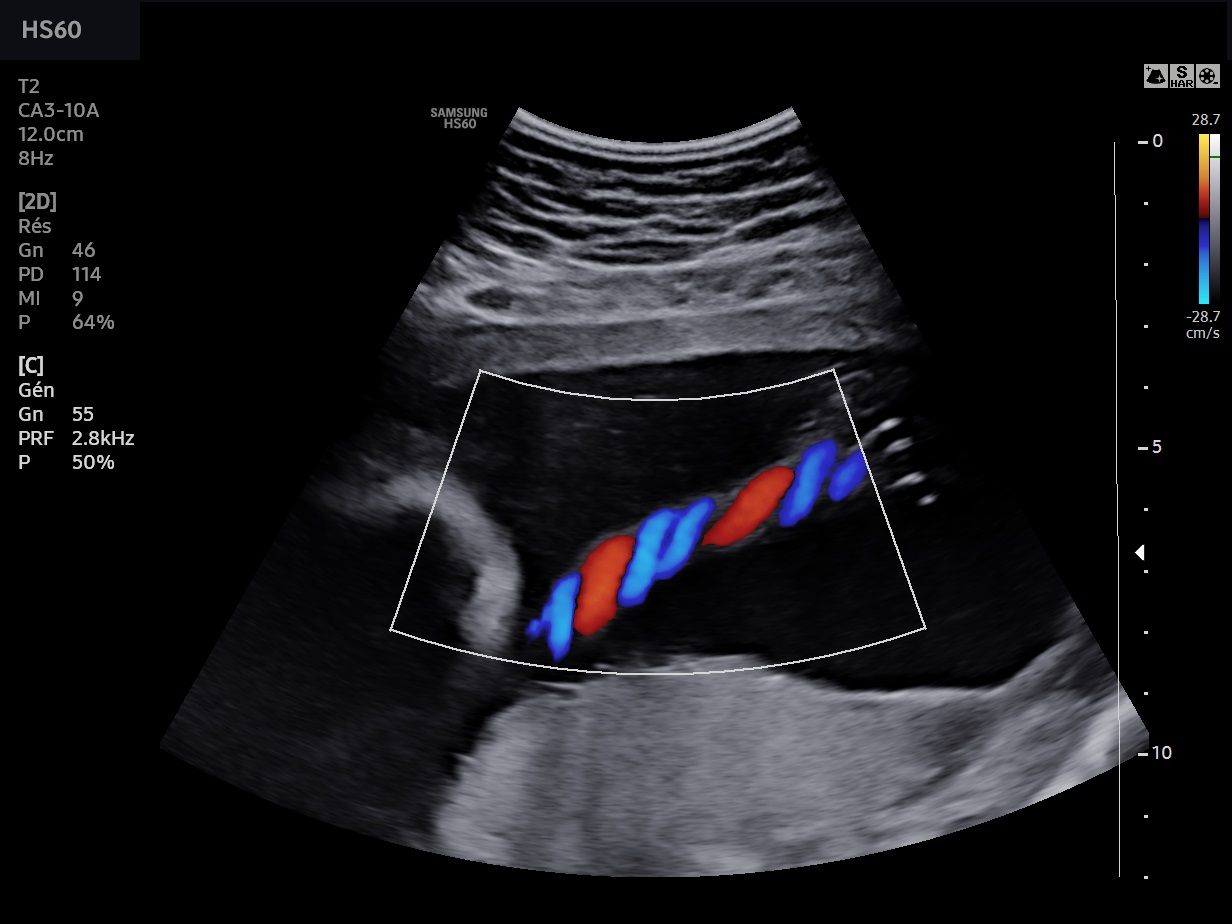

Les sondes de technologie S-Vue™ disposent d'une sensibilité accrue et d'une bande passante plus large que les sondes conventionnelles. Elles garantissent une résolution d’image optimale, même chez les patientes techniquement difficiles. De plus la petite taille et la légèreté de ces sondes améliorent les conditions d'examen au quotidien.

Abdomen, obstétrique, gynécologie, échographie de contraste